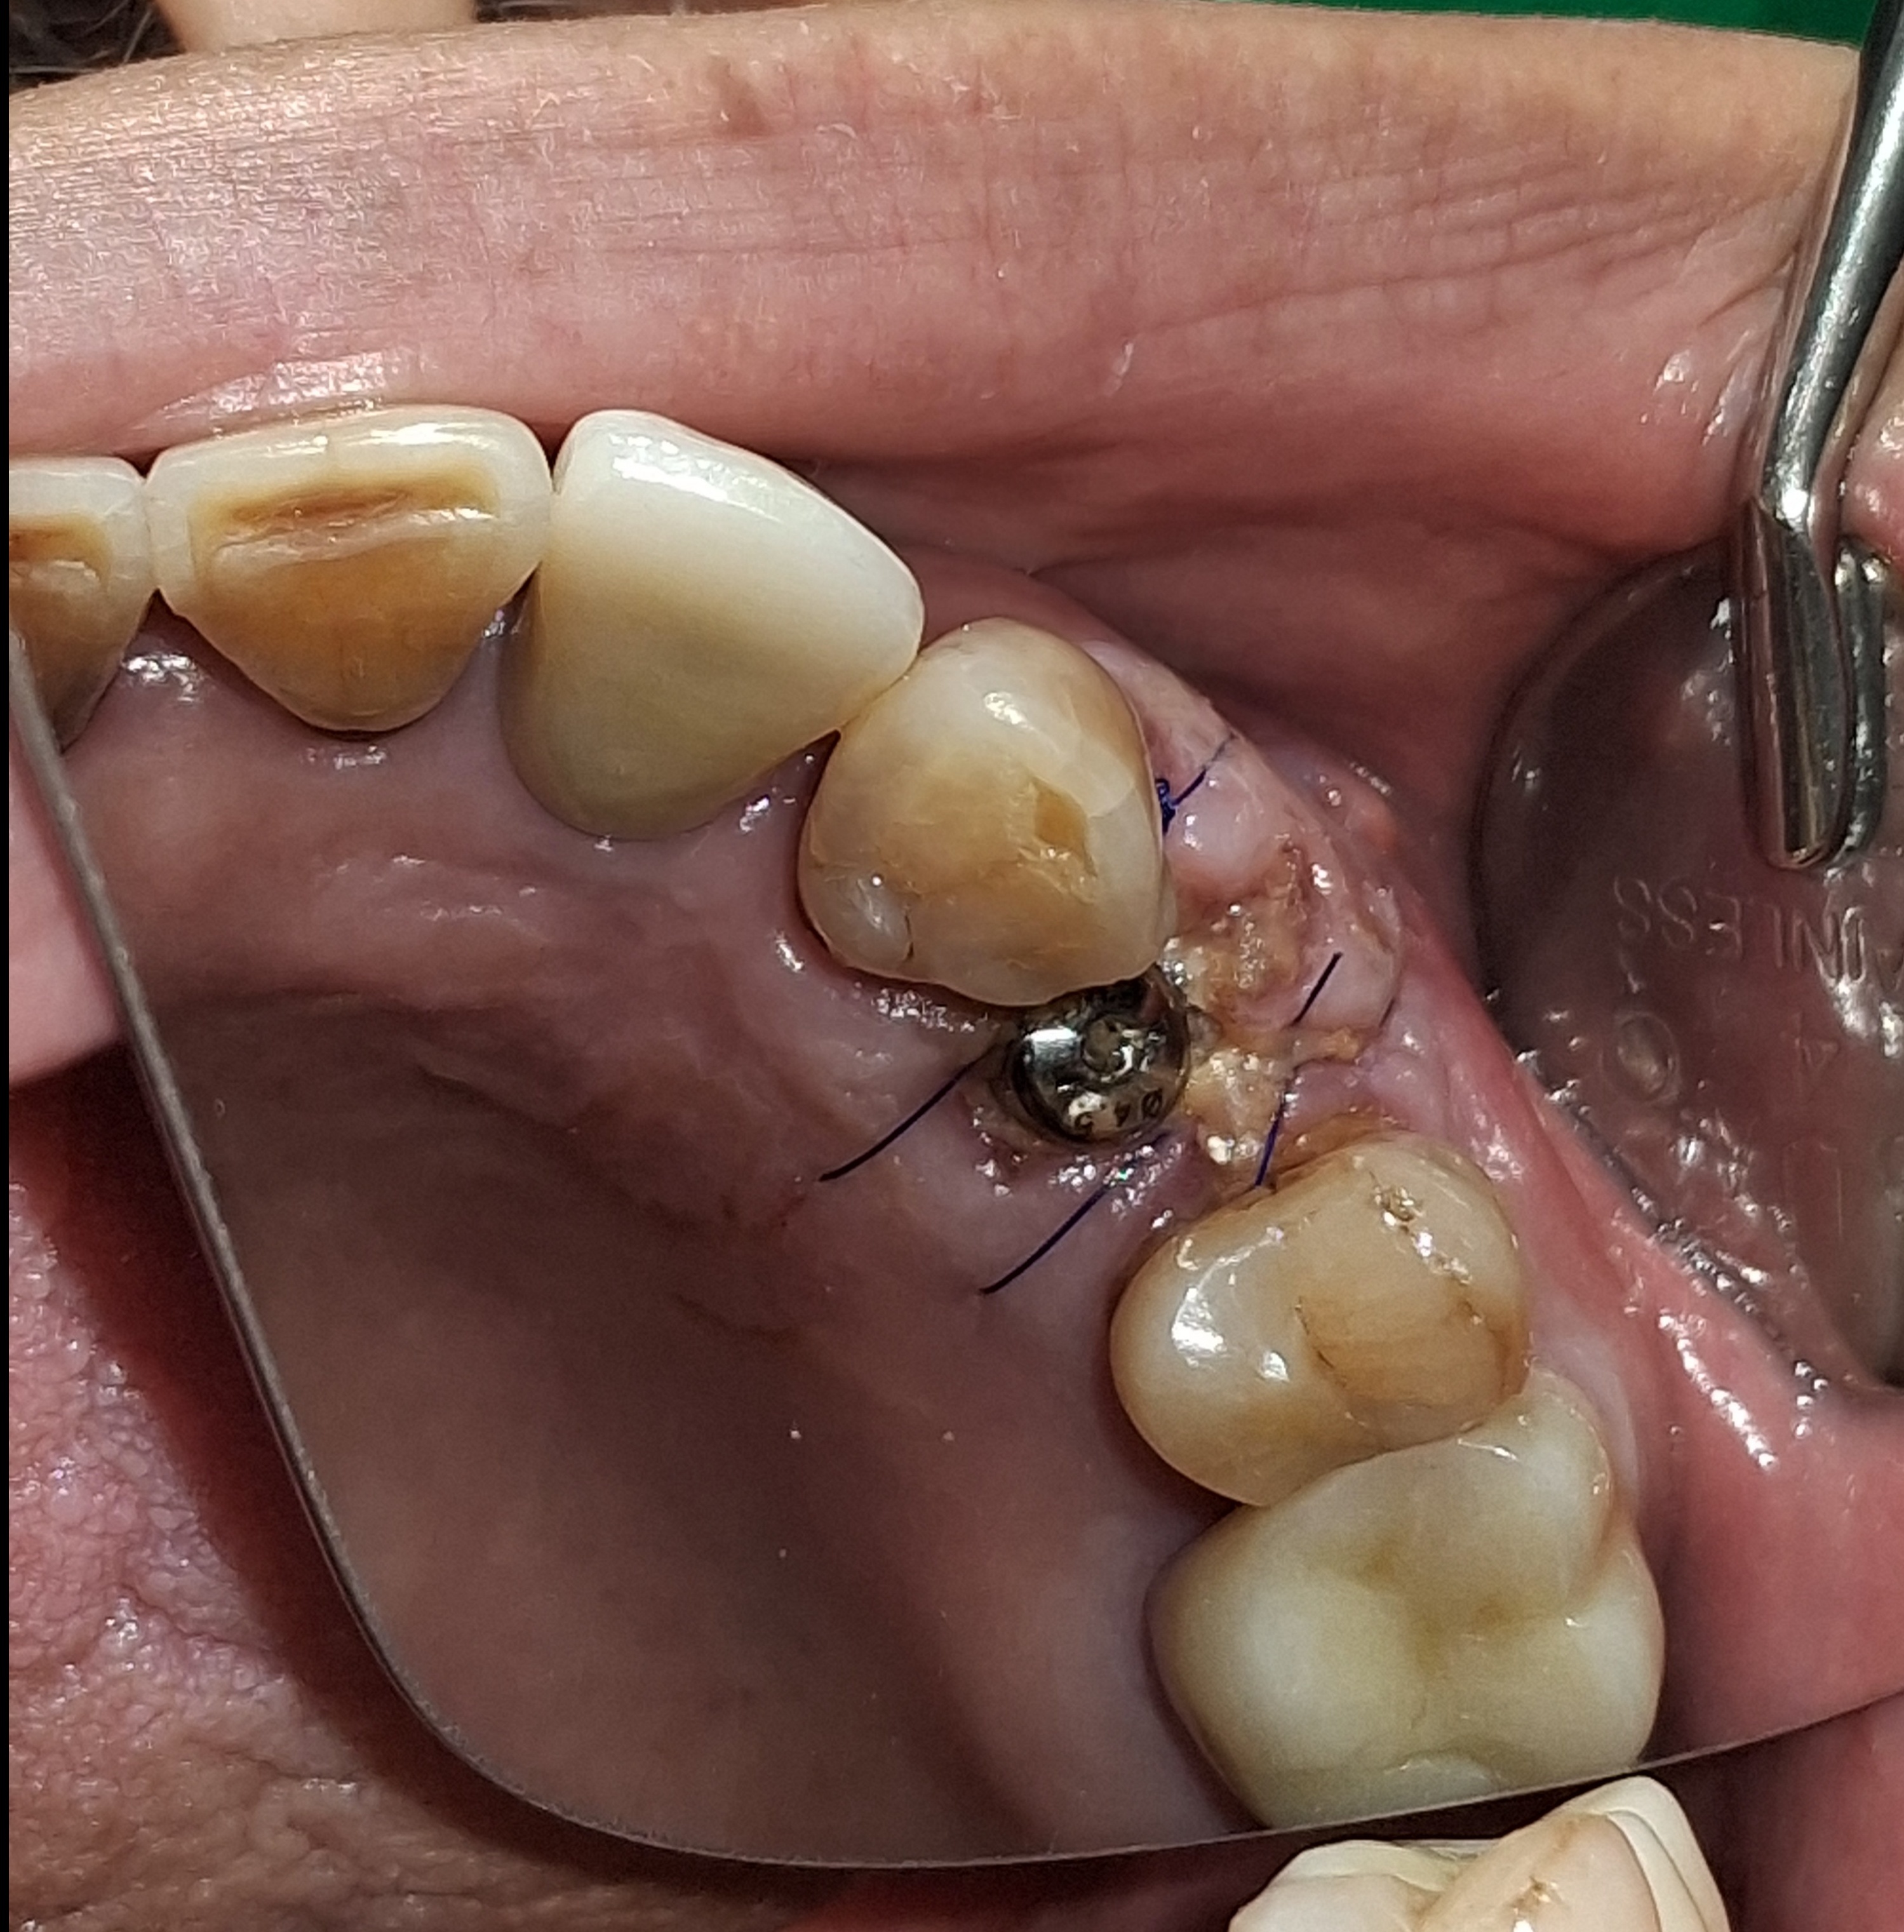

임플란트 시술 사진

임플란트의 5년 성공율은

최근 발표된 논문들까지 종합해도

90~95% 이상으로 발표되고 있습니다.

매우 높은 성공율입니다.

하지만, 실패한 임플란트를 같은 자리에

재식립했을 때의 성공률은 70%대로 떨어집니다.

(J Oral Maxillofac Surg 78:375-385, 2020)

초기에 발견하고 재식립했을 때는 성공율이 높아집니다.